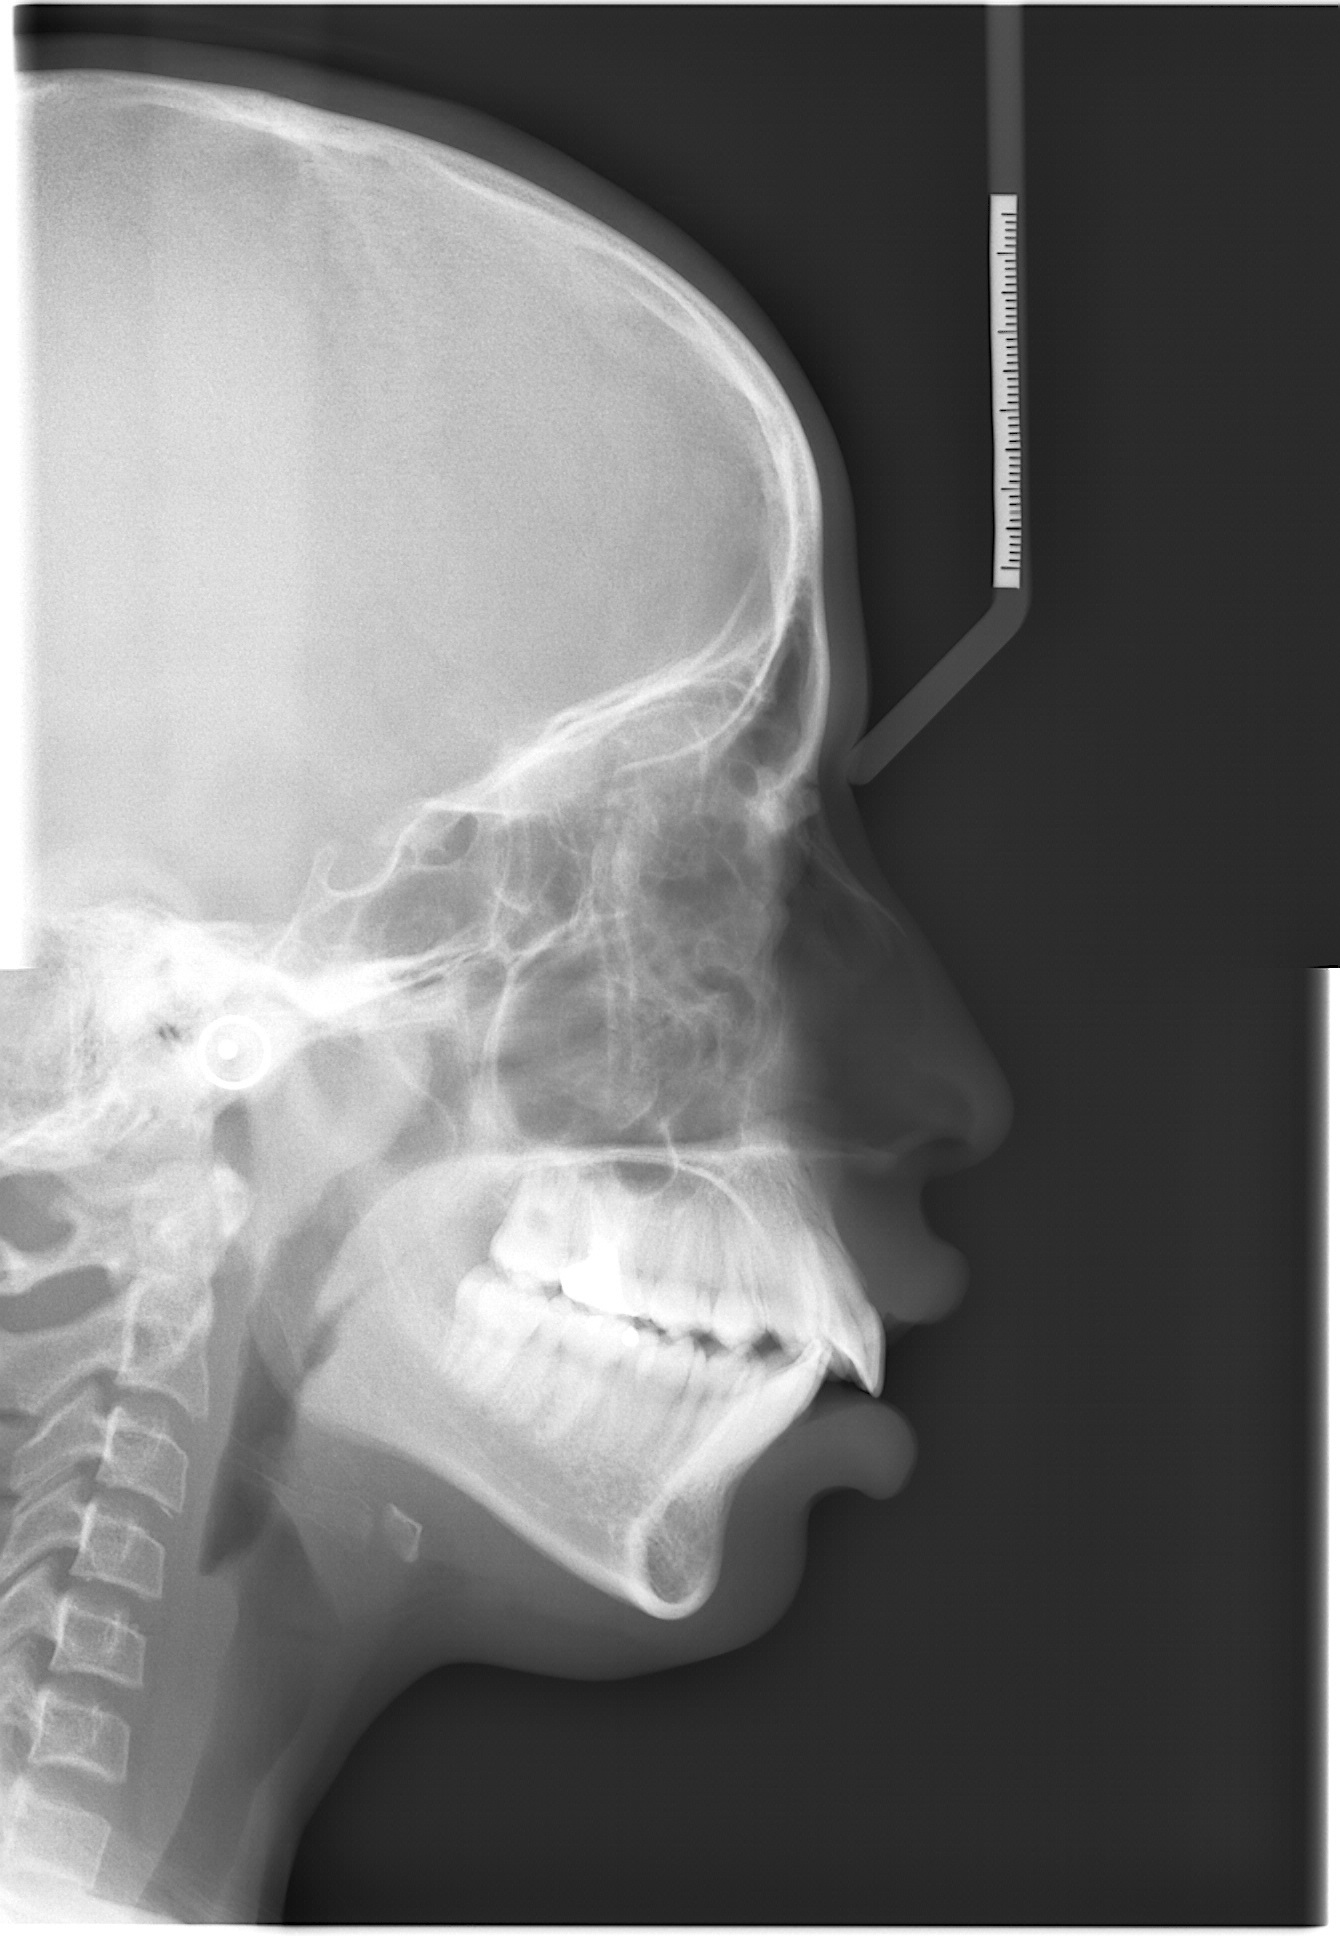

DiverseCeph19: A Cephalometric Landmarks Annotation Dataset

2026-05-06

2.9GB

XRS_1000000021

1692

27

3

Quick View

Data